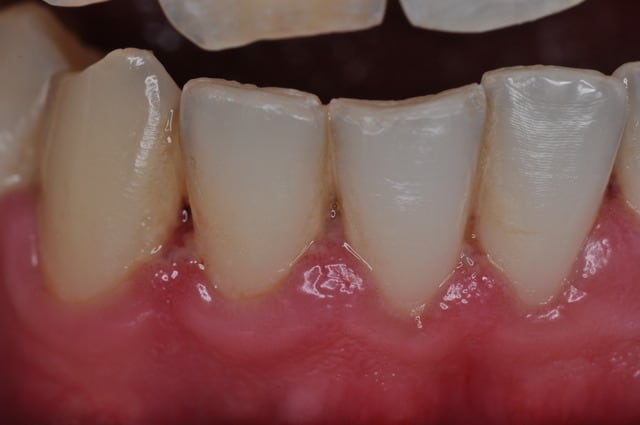

Autre exemple les 2 piliers.

J'ai recadré là, mais sans toucher à la largeur. j'ai juste enlevé en vertical.